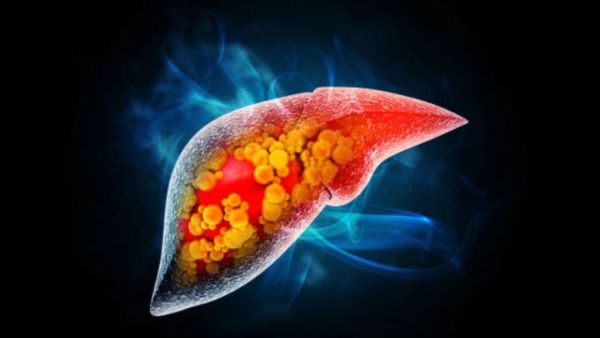

To remove the toxins that are stored in the liver, do it in the diet ‘food’, the fatty liver will be destroyed.